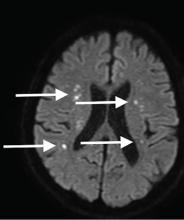

Although CT may underestimate osmotic demyelination syndrome, the typical radiologic findings on brain MRI are hyperintense lesions in the central pons or associated extrapontine structures on T2-weighted and fluid-attenuated inversion recovery sequences.4

Our patient’s clinical course and high hemoglobin A1c suggested prolonged hyperglycemia and high serum osmolality before his admission. After his admission, aggressive hydration and insulin therapy corrected the hyperglycemia and serum osmolality too rapidly for his brain cells to adjust to the change. It was reasonable to suspect a hyperosmolar hyperglycemic state as one of the main causes of his mental status change and ataxia. This, along with lack of improvement in his impaired metal status and new-onset ataxia despite treatment, led to suspicion of osmotic demyelination syndrome. His diminished bilateral knee-jerk and ankle-jerk responses more likely represented diabetic neuropathy rather than osmotic demyelination syndrome.

Osmotic demyelination syndrome has seldom been reported as a complication of hyperosmolar hyperglycemia.6–13 And extrapontine myelinolysis with hyperosmolar hyperglycemia is extremely rare, with only 2 reports to date to the best of our knowledge.6,10